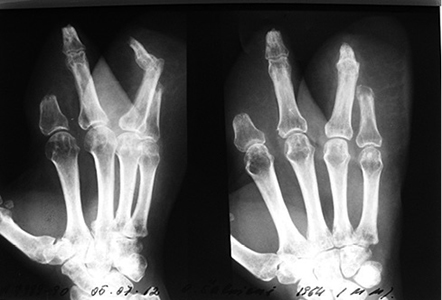

Į VšĮ Respublikinę Vilniaus universitetinę greitosios pagalbos ligoninę 2004 m. spalio mėn. pristatyta 43 m. moteris, patyrusi sunkią traumą – volais buvo nuplėšti kairės plaštakos minkštieji audiniai, per proksimalinius tarppirštakaulinius sąnarius amputuoti II ir V pirštai. Pacientė skubiai hospitalizuota į Plastinės ir rekonstrukcinės chirurgijos skyrių operacinio gydymo. Priimtas sprendimas minkštųjų audinių defektus padengti kirkšnies lopu.

Kairės plaštakos minkštųjų audinių Degloving amputacija. Nugarinis ir delninis paviršiai (1 ir 2 pav.)